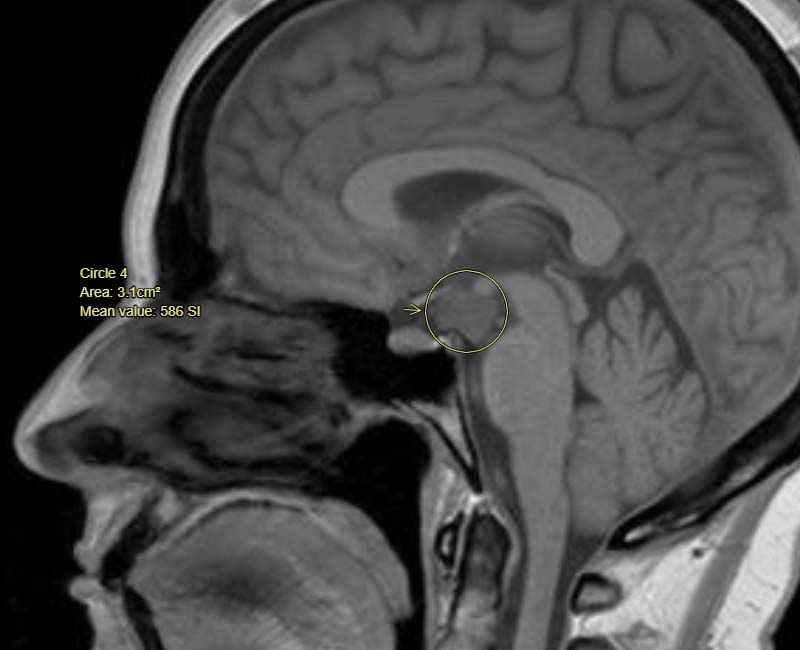

- ไฮโปทาลามัสมีขนาดเล็กมาก (ประมาณขนาดของถั่ว) และอยู่ลึกเข้าไปในสมองของคุณ ดังนั้น การเจริญเติบโตของไฮโปทาลามัสจึงอาจไม่ปรากฏในการตรวจภาพบางอย่าง เช่น การสแกนด้วยซีทีสแกนศีรษะ

การตรวจวินิจฉัยที่สำคัญที่สุดสำหรับ hypothalamic hamartomas คือ MRI ข้อสอบการถ่ายภาพนี้จะสร้างภาพที่มีรายละเอียดสูงในสมองของคุณ เด็กมักต้องการความใจเย็นเล็กน้อย ดังนั้นพวกเขาจึงอยู่นิ่งๆ ระหว่างการตรวจ MRI หากขยับภาพอาจไม่ชัดเจน